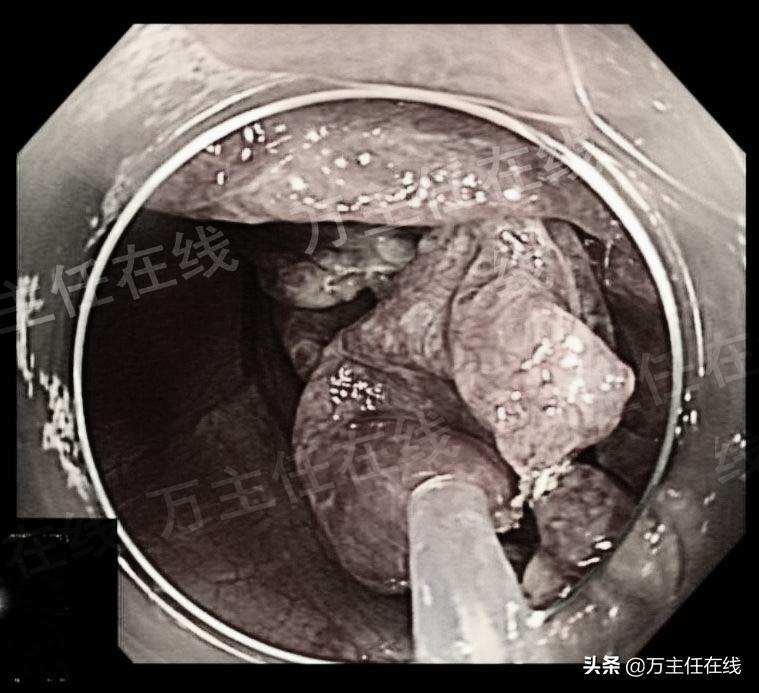

肝囊肿内镜下表现

内镜直视下穿刺引流囊液

内镜直视下打开囊壁(注:原图片可能引起不适已调整)

囊腔内的表现

以圈套器依次切除囊壁(注:原图片可能引起不适已调整)

已切除囊壁后的肝囊肿(注:原图片可能引起不是已调整)